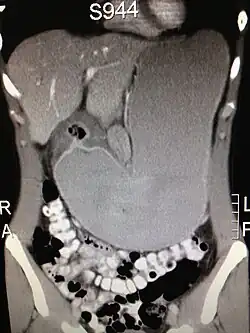

Die ergiebigste Untersuchungsmethode des Magens ist die Gastroskopie (Magenspiegelung). Bei der Magenspiegelung wird oft ein HU-Test zum Nachweis einer Helicobacter-Besiedlung entnommen. Außerdem sind gezielte Biopsien zur histologischen Untersuchung leicht möglich. Die Röntgenuntersuchung des Magens, die vor dem Aufkommen der Gastroskopie betrieben wurde, wird heute nicht mehr routinemäßig durchgeführt, da sie sehr unsichere Ergebnisse produziert. Die Ultraschalluntersuchung des Magens ist leicht möglich, liefert aber nur selten brauchbare Ergebnisse, wie zum Beispiel eine Magenausgangsstenose oder eine auffällige irreguläre Wandverdickung. Beim Ultraschall ist der Magenausgang recht gut, andere Teile wie z. B. die Cardia kaum beurteilbar. Eine Computertomographie des Magens ist ebenfalls nur in Ausnahmefällen sinnvoll. Zur Bestimmung von Helicobacter-Bakterien wird zunehmend ein Atemgastest durchgeführt.